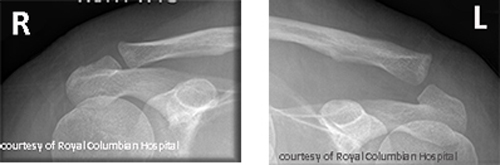

What are the types of AC joint injuries?

Sprain, subluxation (partial dislocation), and complete dislocation.

What causes AC joint injuries and how are they treated?

Fall on shoulder or sports impact; treated with sling or surgery if severe.

What are long-term complications of AC joint injuries?

Pain, arthritis, decreased ROM.

What is the normal range of the AC joint space?

Between 3 mm and 7 mm.